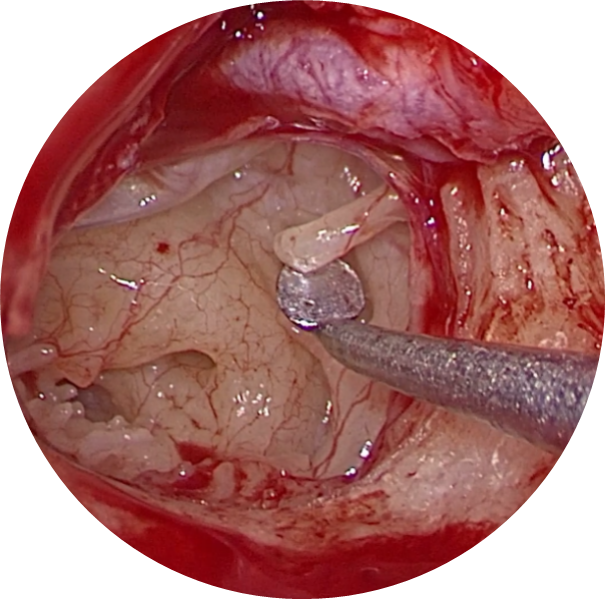

Vue endoscopique peropératoire de l’oreille moyenne (tympan soulevé) :Séparation de l’étrier bloqué du reste des osselets

Vue endoscopique peropératoire de l’oreille moyenne :

Ablation de l’étrier bloqué

Mise en place d’une prothèse en fluoroplastic (piston)